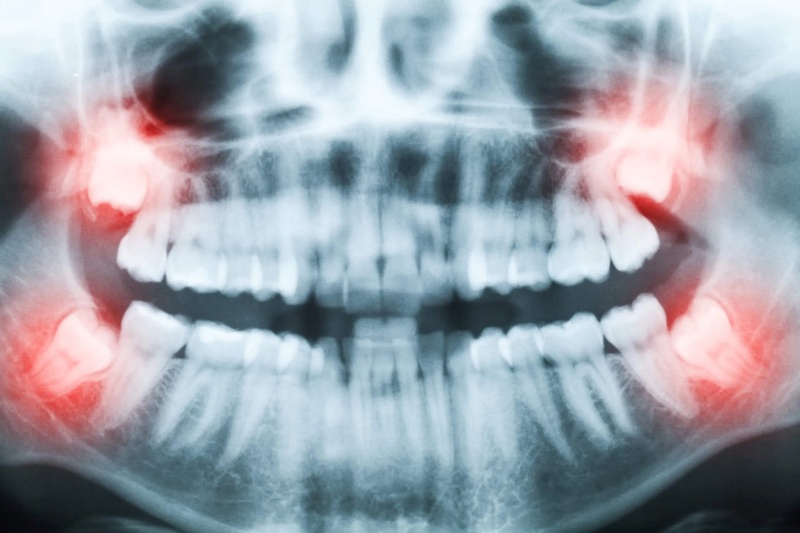

Quy trình nhổ răng được thực hiện trong phòng tiểu phẫu vô khuẩn đạt chuẩn y khoa, bởi đội ngũ bác sĩ chuyên khoa giàu kinh nghiệm trực tiếp thực hiện. Trước khi tiến hành, khách hàng được chụp phim để xác định chính xác vị trí, hướng mọc và mối liên hệ giữa chân răng với dây thần kinh hàm dưới, đảm bảo an toàn tuyệt đối trong suốt quá trình tiểu phẫu.

Đây là một tiểu phẫu phức tạp và có thể tiềm ẩn rủi ro nếu không được thực hiện đúng cách. Tuy nhiên, tại các cơ sở uy tín với bác sĩ tay nghề cao, quy trình diễn ra rất an toàn. Quy trình chuẩn bao gồm các bước: thăm khám, chụp X-quang, gây tê, tiến hành tiểu phẫu và hướng dẫn chăm sóc hậu phẫu.